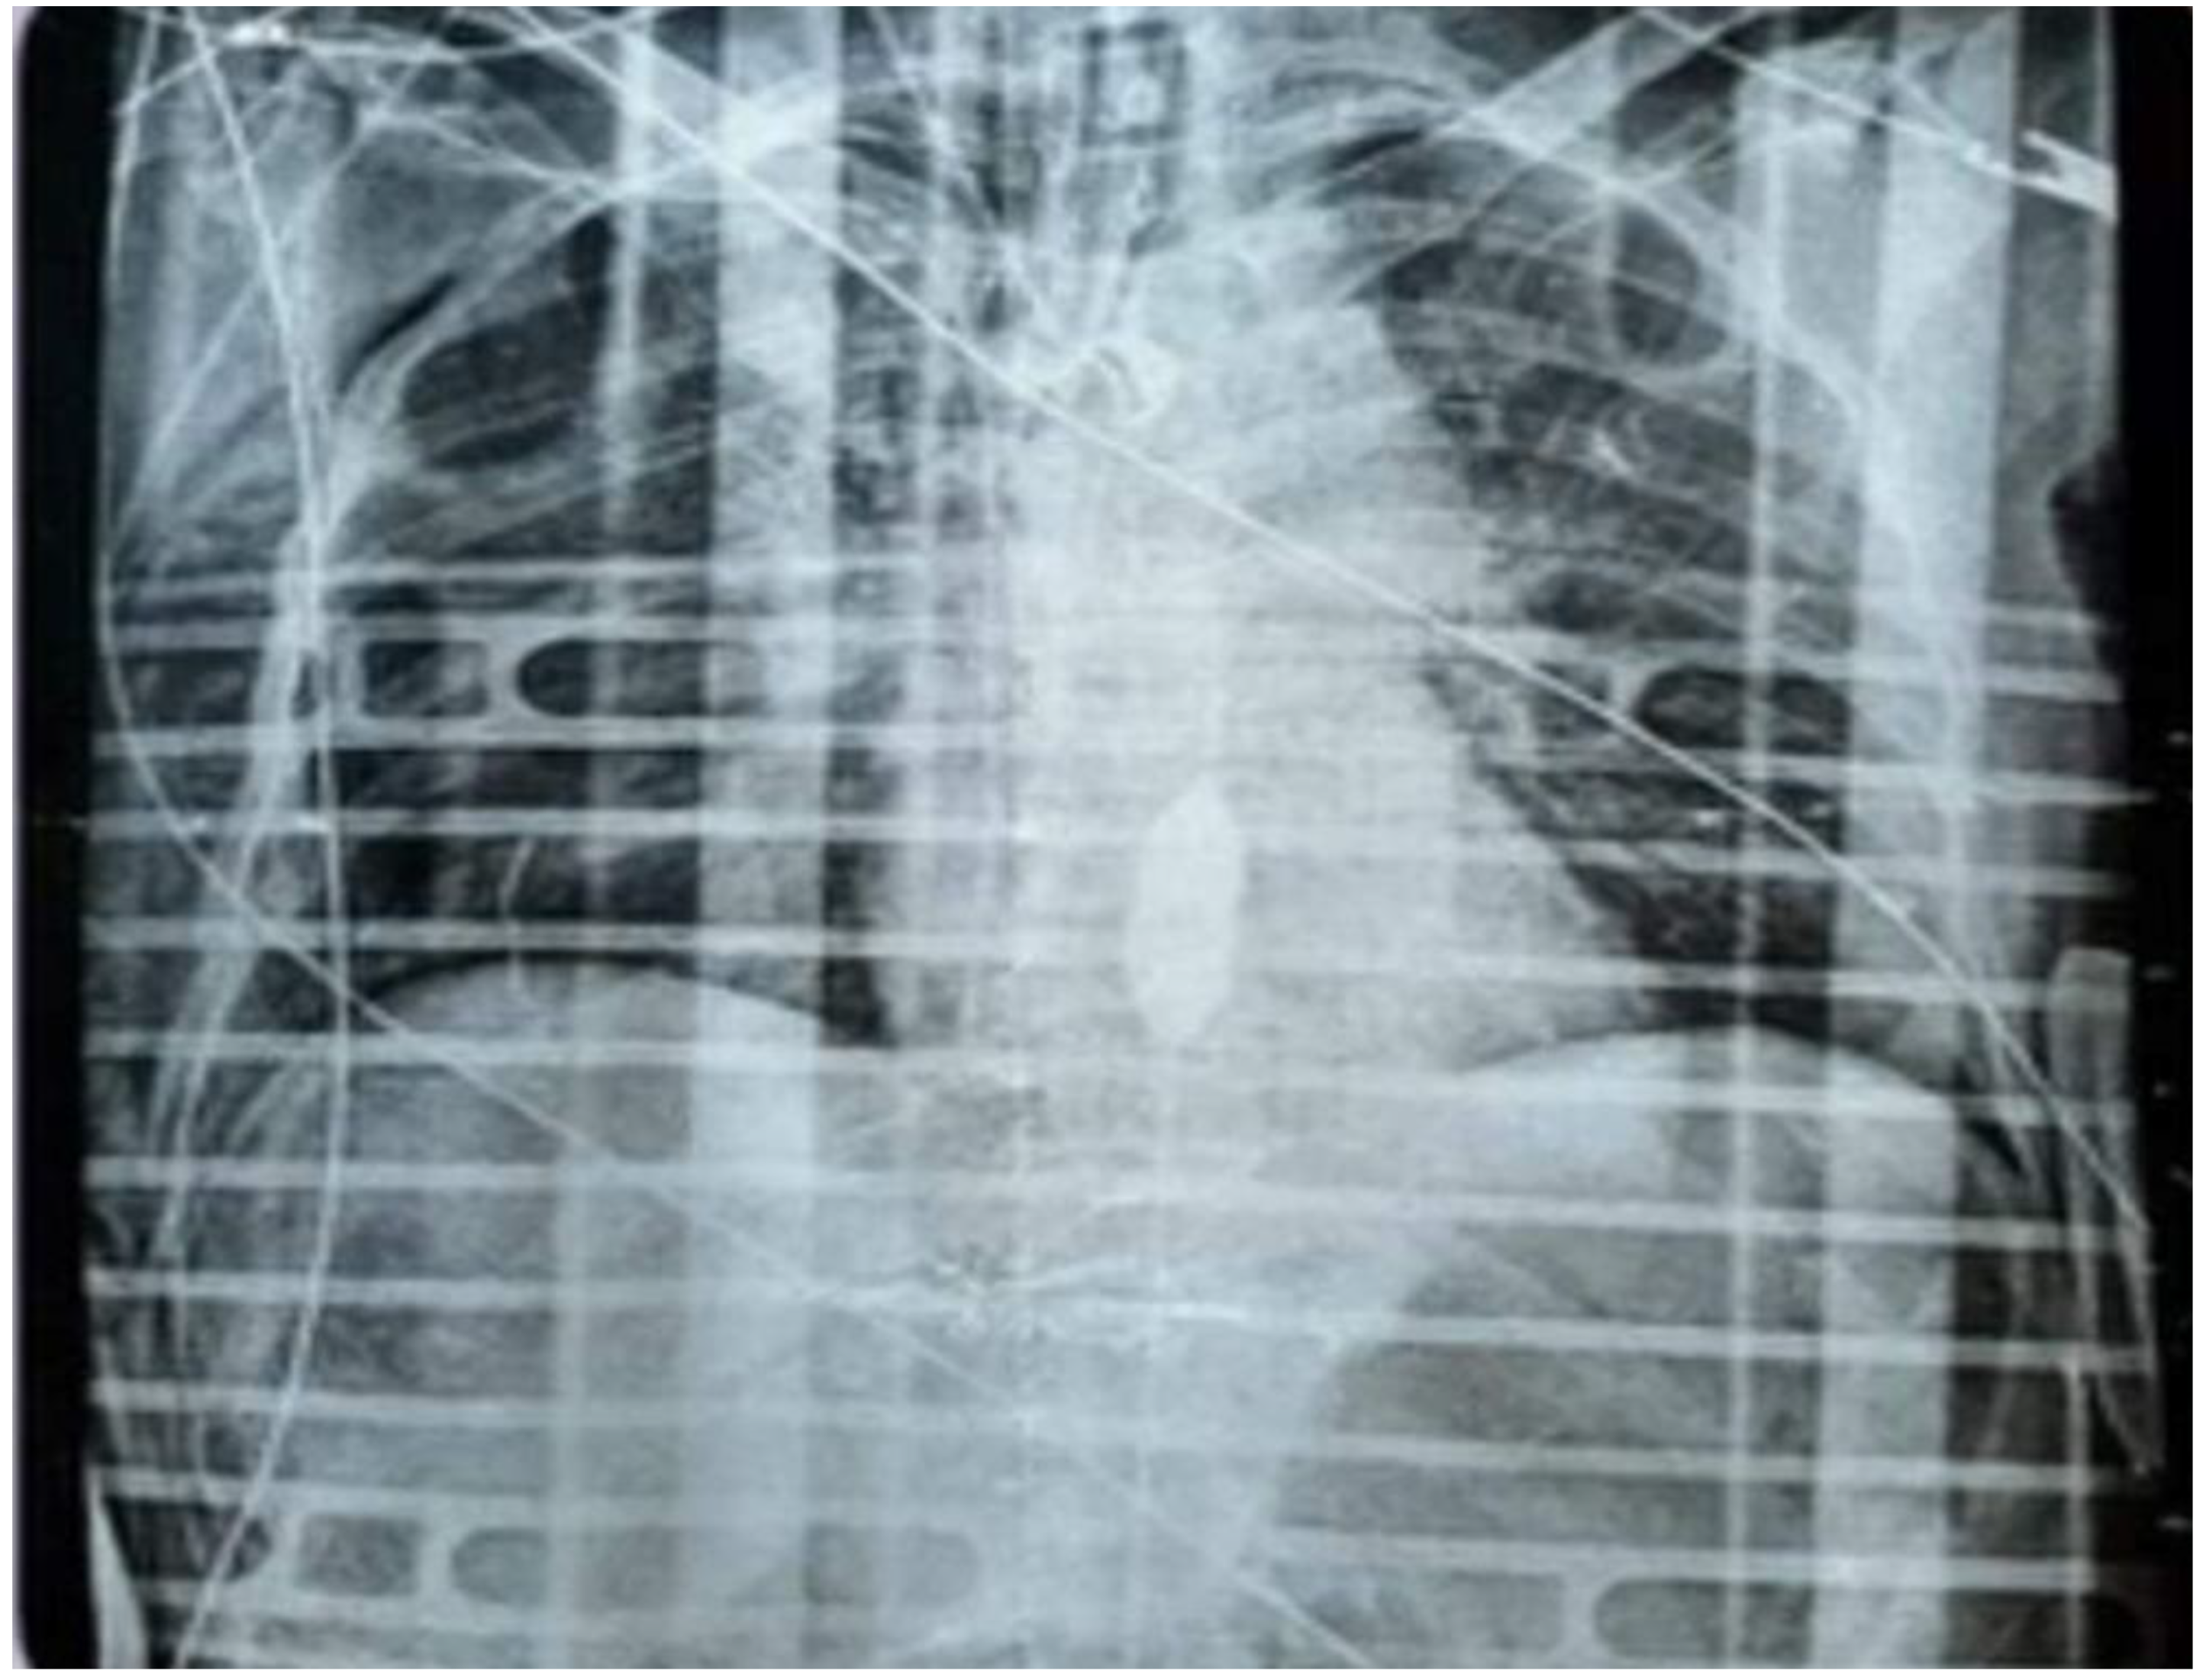

Diagnostic imaging included chest and pelvic radiographs. The chest X-ray demonstrated subcutaneous emphysema of the right chest wall, a small right apical pneumothorax, and displaced fractures of the right 6th rib with non-displaced fractures of the 7th and 8th ribs. A right subclavian central venous catheter was visualized with its tip in the right atrium. The pelvic X-ray revealed a displaced comminuted fracture of the bilateral iliopubic rami, more pronounced on the left side, and a fracture of the left acetabulum with misalignment of bone fragments.

Despite aggressive resuscitative efforts, the patient's hemodynamic condition deteriorated, culminating in cardiac arrest with ventricular fibrillation observed on the monitor. Defibrillation was attempted without return of spontaneous circulation, and pulseless electrical activity ensued. Given the critical situation, a REBOA® catheter was urgently inserted using the blind method and positioned in Zone 1 of the aorta during ongoing chest compressions facilitated by an automated CPR device (LUCAS®). Correct placement was assessed by verifying the device’s centimeter markings. This intervention successfully restored a palpable central pulse, temporarily stabilizing the patient's circulation with a blood pressure of 155/62 mmHg and a heart rate of 110 bpm.

Following return of spontaneous circulation, the patient was transferred to the radiology department for a full-body contrast-enhanced CT scan. Imaging revealed a significant aortic rupture extending from the aortic isthmus to the arch. It was noted that the REBOA® balloon had been inadvertently placed within a false lumen, necessitating repositioning under radiological guidance. Additional findings included burst fractures of the thoracic vertebrae at T5 and T9, a comminuted pelvic fracture, a transverse fracture of the sacrum at S3, and a blowout fracture of the left acetabulum (Figure 1).

Figure 1. Correct placement of the REBOA in Zone 1 (blind insertion by assessing the device’s centimeter scale. Device insertion during chest compressions with the Lucas automatic CPR device (patient in cardiac arrest).